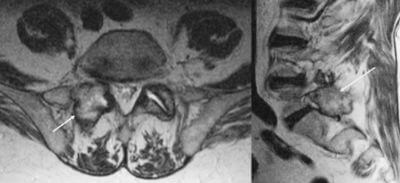

Gout In Back Image

Gout In Shoulder

I never had an episode of gout before this one. Shoulder. Detected by MRI and my visit to an orthopedic surgeon. The episode was horribly painful. The reversal (cure) has been fairly swift.